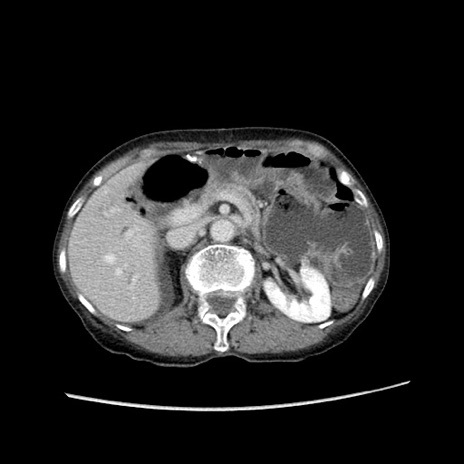

症例25(横断像)

【症例】80歳代女性

【主訴】胸のつかえ感

【現病歴】約9時間前に食後から胸のつかえた感じあり、嘔吐あり、来院。

【既往歴】胃癌(全摘)、胆摘、虫垂炎

【身体所見】心窩部に圧痛あり、反跳痛なし。

【データ】WBC 5700、CRP 0.05